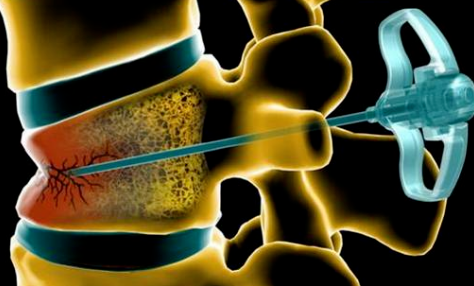

②高龄患者无明确禁忌者,可行微创经皮骨水泥椎体成形术。

图片